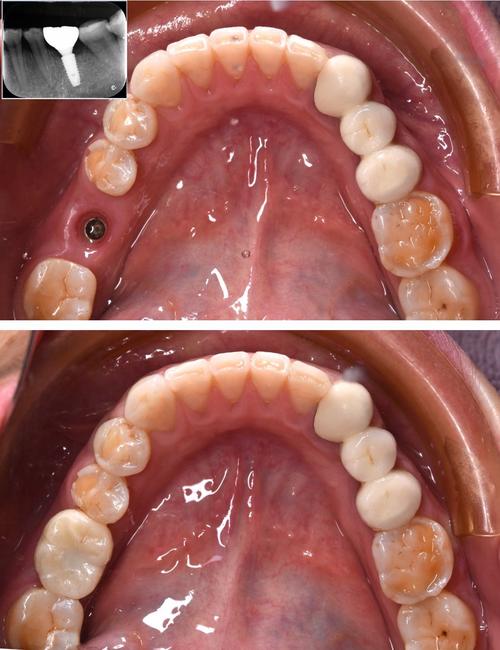

“种牙”的学名是“种植义齿修复”,是一种针对牙齿缺失的修复方式,当牙齿完全缺失(如拔牙后),医生会在牙槽骨内植入一个纯钛制成的“种植体”(相当于人工牙根),待种植体与牙槽骨紧密结合(骨结合,通常需要3-6个月)后,再在种植体上方安装基台和牙冠,最终恢复缺失牙的功能和美观。

种牙的核心是“替代天然牙根”,通过手术将种植体植入牙槽骨,模拟自然牙的结构(种植体+基台+牙冠),种植体的生物相容性极佳,能与骨组织形成牢固结合,因此被称为“人类的第三副牙齿”,种牙的流程包括:术前检查(CBCT评估骨量)→种植体植入手术→骨结合期→基台安装→牙冠制作与戴入,治疗周期较长(3-6个月),费用相对较高,但使用寿命长,维护得当可使用终身。

(图片来源网络,侵删)- 牙齿大面积缺损,仅剩牙根(如前牙外伤折断至牙龈下,后牙大面积龋坏导致只剩牙根);